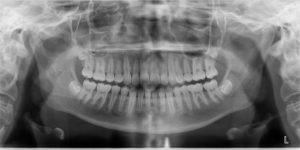

An 11.3 year old caucasian female presents with a chief concern that “my teeth don’t come together.”